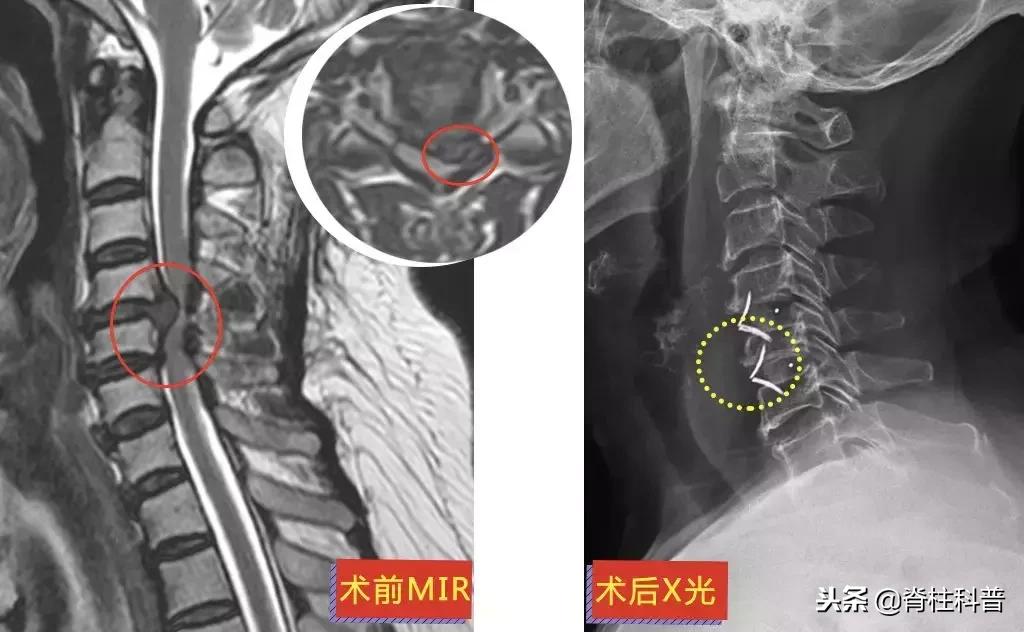

和大部分病人一样,为了避免手术治疗,他们都“竭尽所能”。牵引、针灸、推拿治疗是常见的保守治疗方法,保守治疗的效果如何,需要根据不同的病情来做判断,在此按下不表。下面这位黄三叔经过“脱水治疗”,却是效果欠佳。

▲ 黄三叔:术前MRI与术后X光